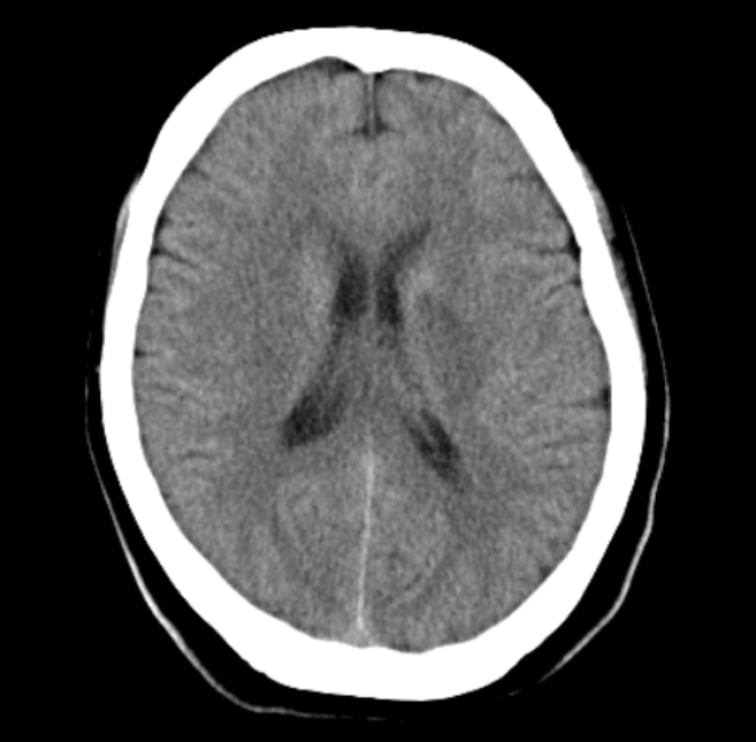

- CT画像情報から頭蓋内の高吸収・低吸収領域を抽出

頭部単純CTの画像情報から頭蓋内の高吸収・低吸収領域を抽出し強調表示をします

- 頭部単純CTの画像情報から頭蓋内の高吸収・低吸収領域を抽出し強調表示をします

- 頭蓋内で前後のスライス及び同一スライス内の左右で比較して組織構造もしくは組織境界の不明瞭化が見られる領域を表示します

- 抽出領域がセグメンテーション表示されることで視覚的な確認が可能です